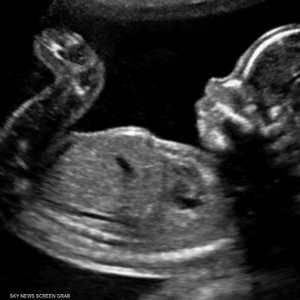

تواجه الكثير من النساء صعوبات في حدوث الحمل لأسباب مختلفة قد يبدو بعضها معقدا، لكن ما لا تدركه الكثيرات، أن مشكلات بسيطة وغير متوقعة قد تكون سببا في تأخر الإنجاب.